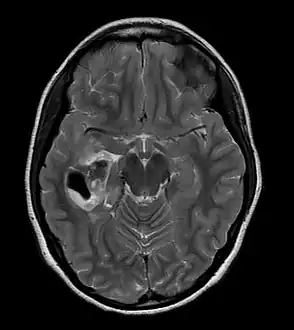

Pleomorphic xanthoastrocytoma (WHO grade II); Pleomorphic xanthoastrocytoma represents a distinctive glioma subtype

PXA as visualized on an MRI